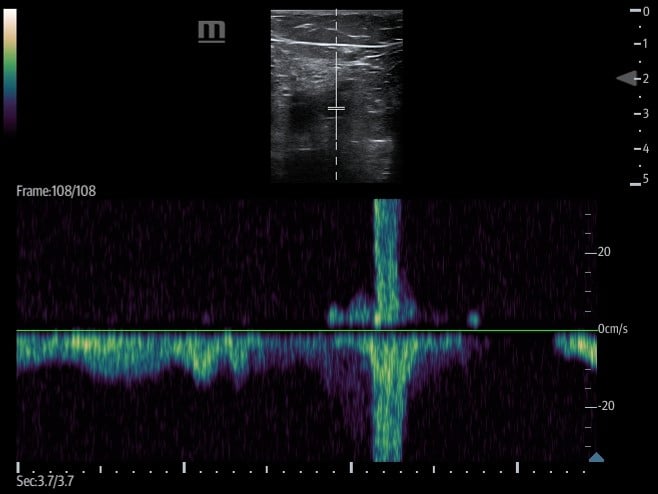

- Respiratory variation/phasic flow

- Involves placing the transducer on the leg, typically at the CFV, and setting the ultrasound machine to spectral (pulsed wave) Doppler mode.

- Flow velocity in deep venous structures varies with the respiratory cycle and changes in intrathoracic pressure.

- A lack of variation in flow may be suggestive of an obstructive process (eg, thrombus, compressive pathology) along the venous system between the proximal inferior vena cava and point of transducer placement. (Figure 17)

- Figure 17. Respiratory variation seen at the CFV with Pulsed wave Doppler.